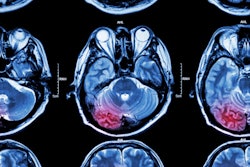

CT radiation doses have decreased significantly over the past decade, but more work needs to be done to manage radiation dose in children, adolescents and young adults, according to Spanish-led research.

The authors studied the radiology records of 276 hospitals linked to population-based cancer registries and looked at nearly 950,000 patients who underwent a CT scan before the age of 22. Their new data and analysis on radiation dose deserve a close look. Find out more in our CT content area.